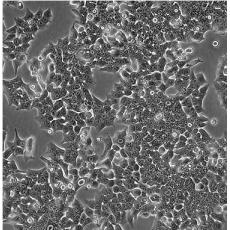

HCT 116

產(chǎn)品名稱 HCT 116

中文名稱 人結(jié)直腸腺癌細胞

組織來源 結(jié)腸腺癌;男性

生長特性 adherent

形態(tài)特征 epithelial

細胞描述 The cells are positive for keratin by immunoperoxidase staining.HCT 116 cells are positive for transforming growth factor beta 1(TGF beta 1) and beta 2(TGF beta 2) expression.